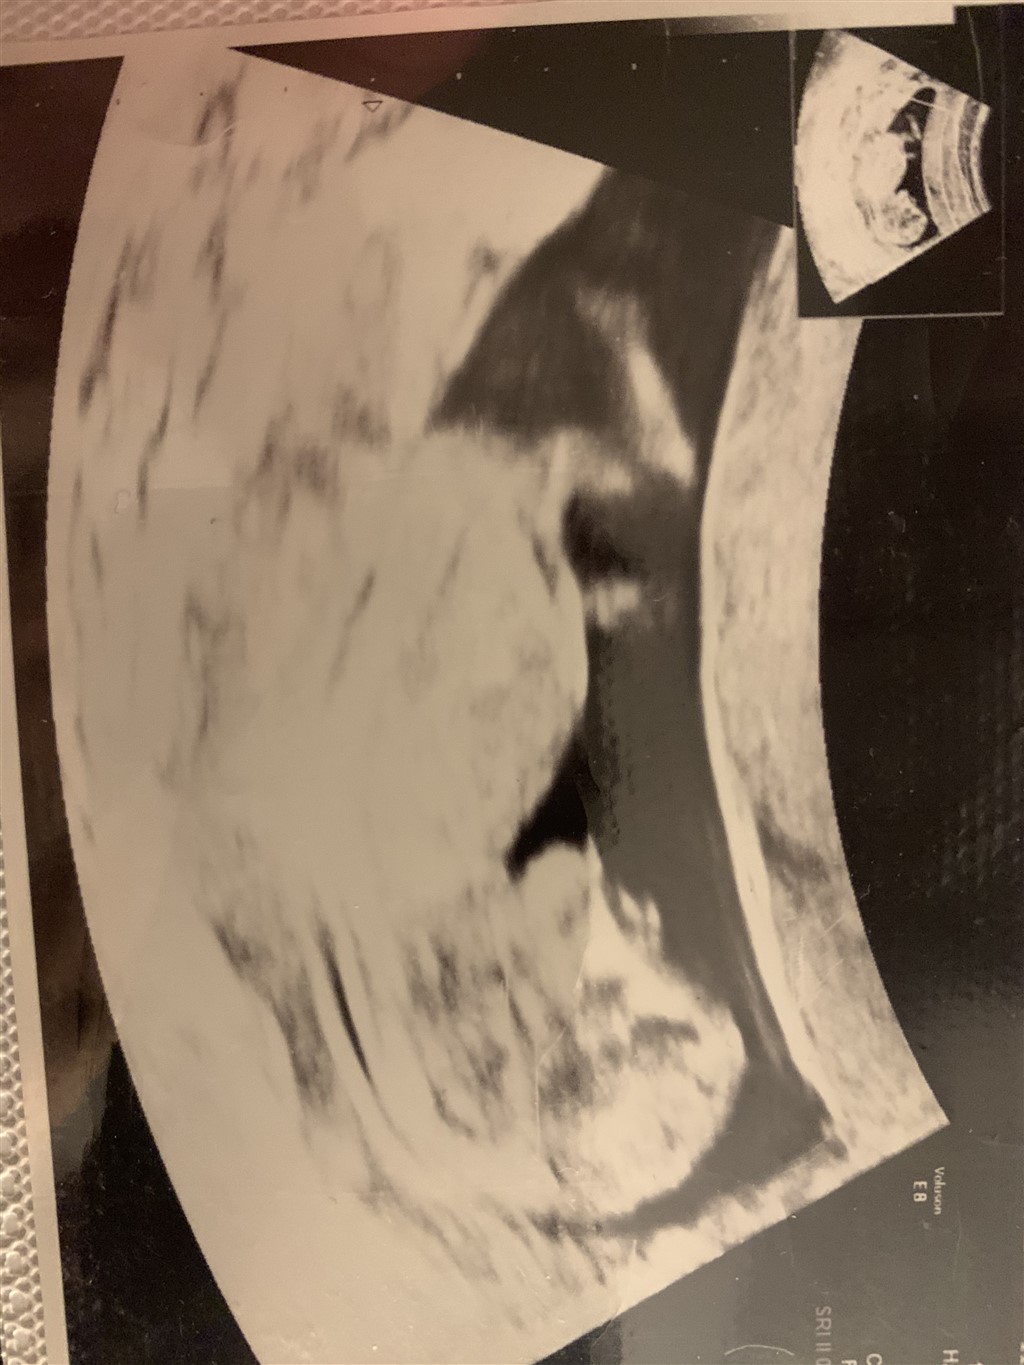

Jeg tror at alt er nemmer at se nu større fosteret/baby er, så jeg tænker en uge skulle man jo vælge, og ved 14+0 er man måske bare sikker på man kan sige det med sikkerhed. Jeg tror måske man kan se før hos nogen, og senere end de 14+0 hos andre

Nu er nub-teorien jo ikke noget nyt, men normalt siger man, at den først kan bruges fra 12+4. Men ja, hun tilbyder ganske rigtigt, man kan sende et billede og få et bud på køn efter 12+0. Hun skriver også selv, at den egentlige kønsudvikling først starter fra uge 11+.

Men det var ikke min pointe. Min pointe er, at din konspirationsteori omkring kønsscanning og abortgrænse ikke giver mening. Man scanner ikke efter køn generelt før 14+0, fordi det simpelthen er for usikkert. Det har intet at gøre med abortgrænsen.